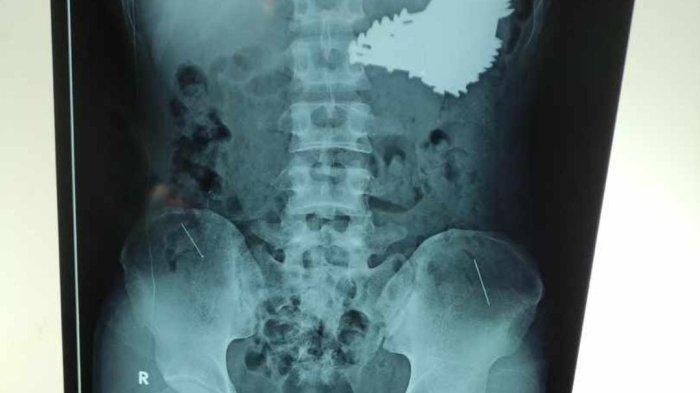

Dari informasi itu, dokter melakukan pemeriksaan radiologi dan pemeriksaan rontgen.

Foto rontgen itu memperlihatkan ada banyak paku berukuran besar yang bersarang di dalam lambung.

Saat ini, paku-paku yang bersarang di lambung Slamet sudah berhasil diangkat. Total ada 70 batang paku di dalam perutnya.